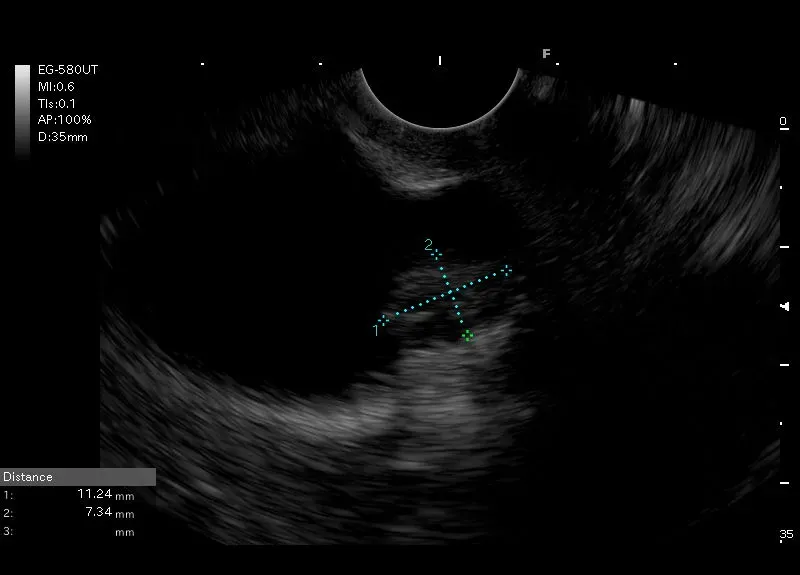

Widoczna w pęcherzyku żółciowym, przyścienna, hyperechogeniczna zmiana wielkości

około 11/7mm, zawierająca torbiel 4 mm - obraz odpowiadać może adenomiomatozie.